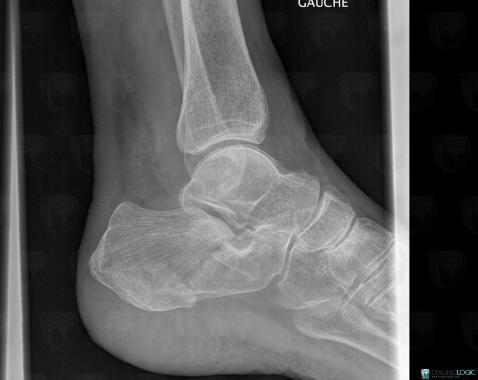

Fracture, Calcaneus, X rays

Here is the specific information in the key image above:

- Diagnosis Fracture, Location(s) Calcaneus, with gamuts